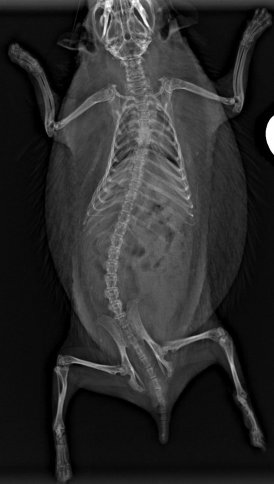

Может мне повезло, но крошик ниразу ни чем не болел. Единственный раз когда обратился к специалисту это когда у него нога застряла под дверью и он видимо вытаскивая ее повредил. Начал сильно хромать, запинаться при ходьбе. Поэтому я повез его в ветеринарку. Это был их первый случай когда привозили ежа🤣 собрался прям весь персонал делать рентген ежу. К счастью обошлось без переломов, просто ушиб мягких тканей. Фоток к сожалению не сохранилось, но вот для примера

Было примерно так же)